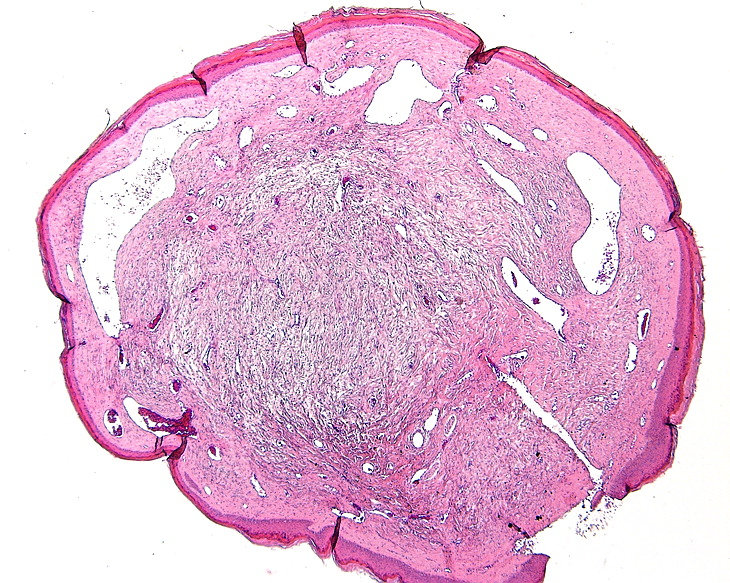

PA:Histologisch gaat het om bolvormige fibreuze tumoren

met een prominente vasculaire component, gelegen in de papillaire dermis. De

overliggende epidermis is atrofisch. Een haarfollikel kan aanwezig zijn in of

nabij de rand van de laesie. De oorspronkelijke naam trichodiscoma suggereert

dat de laesies uitgaan van de 'haardisk', maar daarover is twijfel. Daarom is

de naam discoid fibroma beter. Klinisch zijn het ook kleine ronde schijfvormige

oppervlakkig gelegen tumortjes. Een ‘haardisk’ werd in 1902 beschreven door

Pinkus als een mechanoreceptief adnexaal orgaantje, bestaande uit een schijf

rond de haar, rijk gevasculariseerd, waarin Merkelcellen en dikke gemyeliniseerde

zenuwuiteinden, en bekleed met een dikke epidermis.